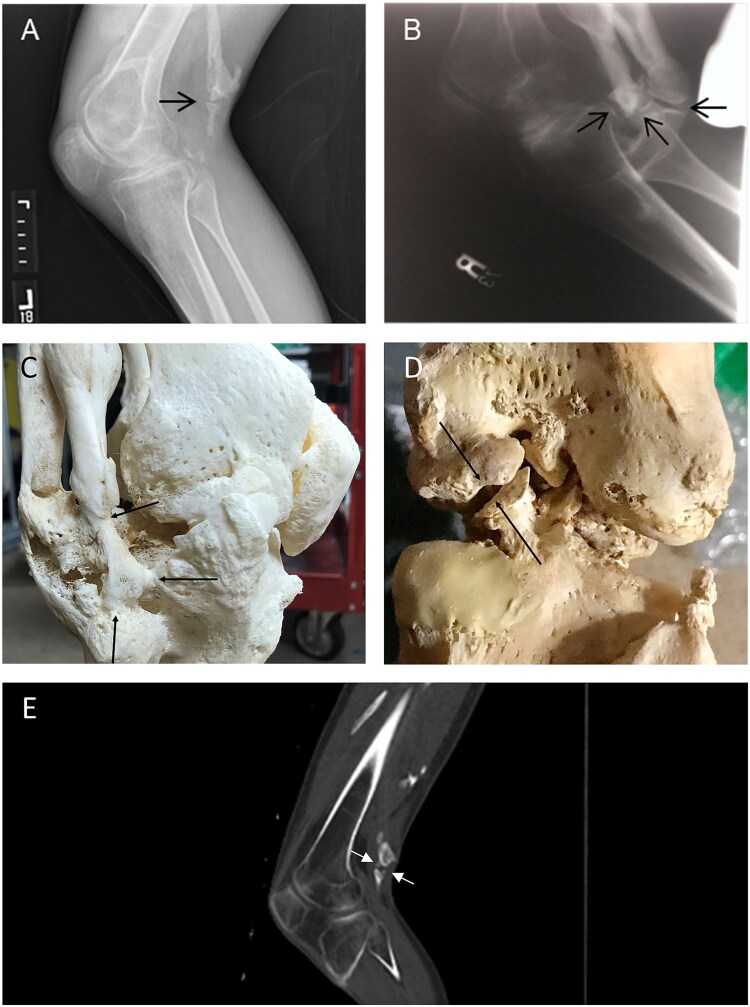

假关节(假关节)是正常异位骨骼骨折愈合的并发症,但在异位部位未见报道。进行性骨化纤维发育不良(FOP)是一种极其罕见的遗传性疾病,其特征是进行性异位骨化(HO)和先天性骨骼异常,包括正常位置骨骼的发育性关节病。在这里,我们报告了6例FOP患者的异位假关节形成,所有这些患者都发生在疼痛发作和膝关节、髋关节和前臂软结缔组织的HO之后。据我们所知,FOP是唯一发生异位假关节形成的人类疾病。这些发现支持来自突变ACVR1的BMP通路信号失调不仅介导HO,还介导异位假关节的形成,并且异位假关节可以由新生的肌肉骨骼元件引起。

Pseudoarthroses (false joints) occur as a complication of fracture healing in the normotopic skeleton but have not been reported at ectopic sites. Fibrodysplasia ossificans progressiva (FOP) is an ultra-rare genetic disorder characterized by progressive heterotopic ossification (HO) and congenital skeletal abnormalities including developmental arthropathy in the normotopic skeleton. Here, we report ectopic pseudojoint formation in 6 patients with FOP, all occurring after painful flare-ups and HO in soft connective tissues of the knee, hip, and forearm. To our knowledge, FOP is the only human condition in which ectopic pseudojoint formation occurs. These findings support that dysregulated BMP pathway signaling from mutant ACVR1 mediates not only HO, but also ectopic pseudojoint formation, and that ectopic pseudojoints can arise from de novo musculoskeletal elements.